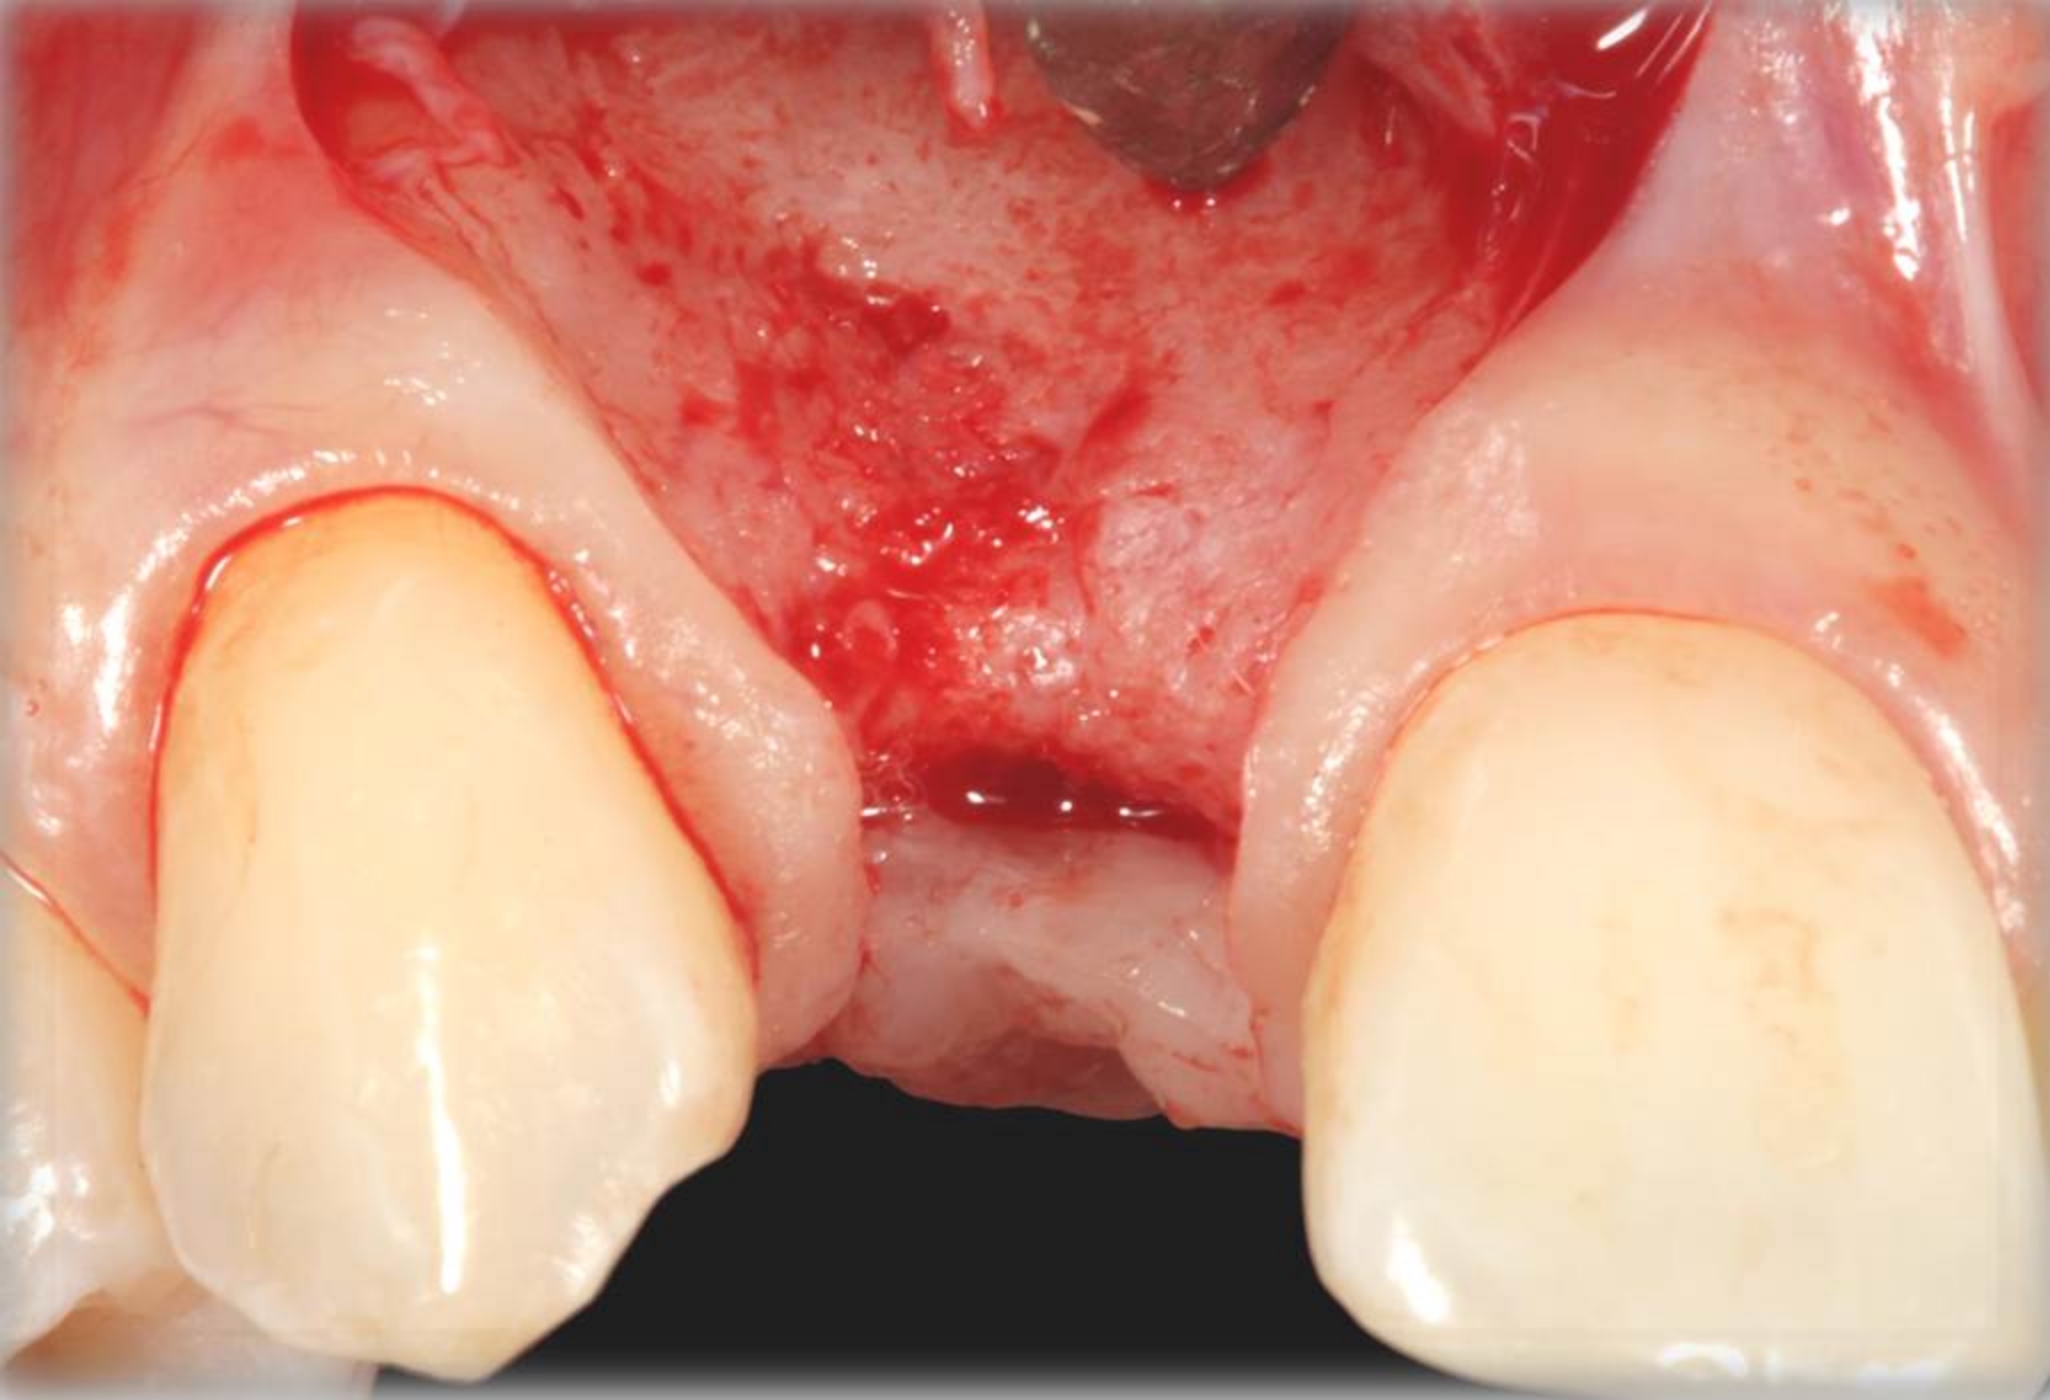

Fig 20. Papillae-sparing incisions were developed both horizontally and vertically. The pedicle flap was elevated, exposing a thin ridge.

Figure 20